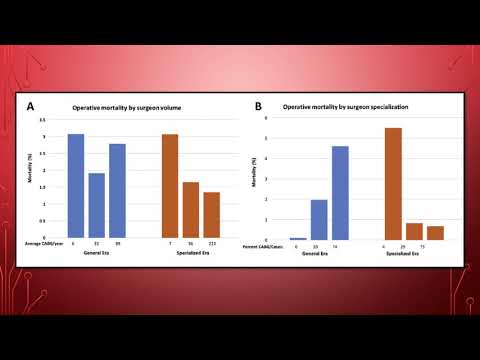

La especialización quirúrgica y programática mejora la mortalidad en la cirugía de revascularización miocardica. Dra. Ana Laura Mori. Residencia de Cardiología. Hospital C. Argerich. Buenos Aires